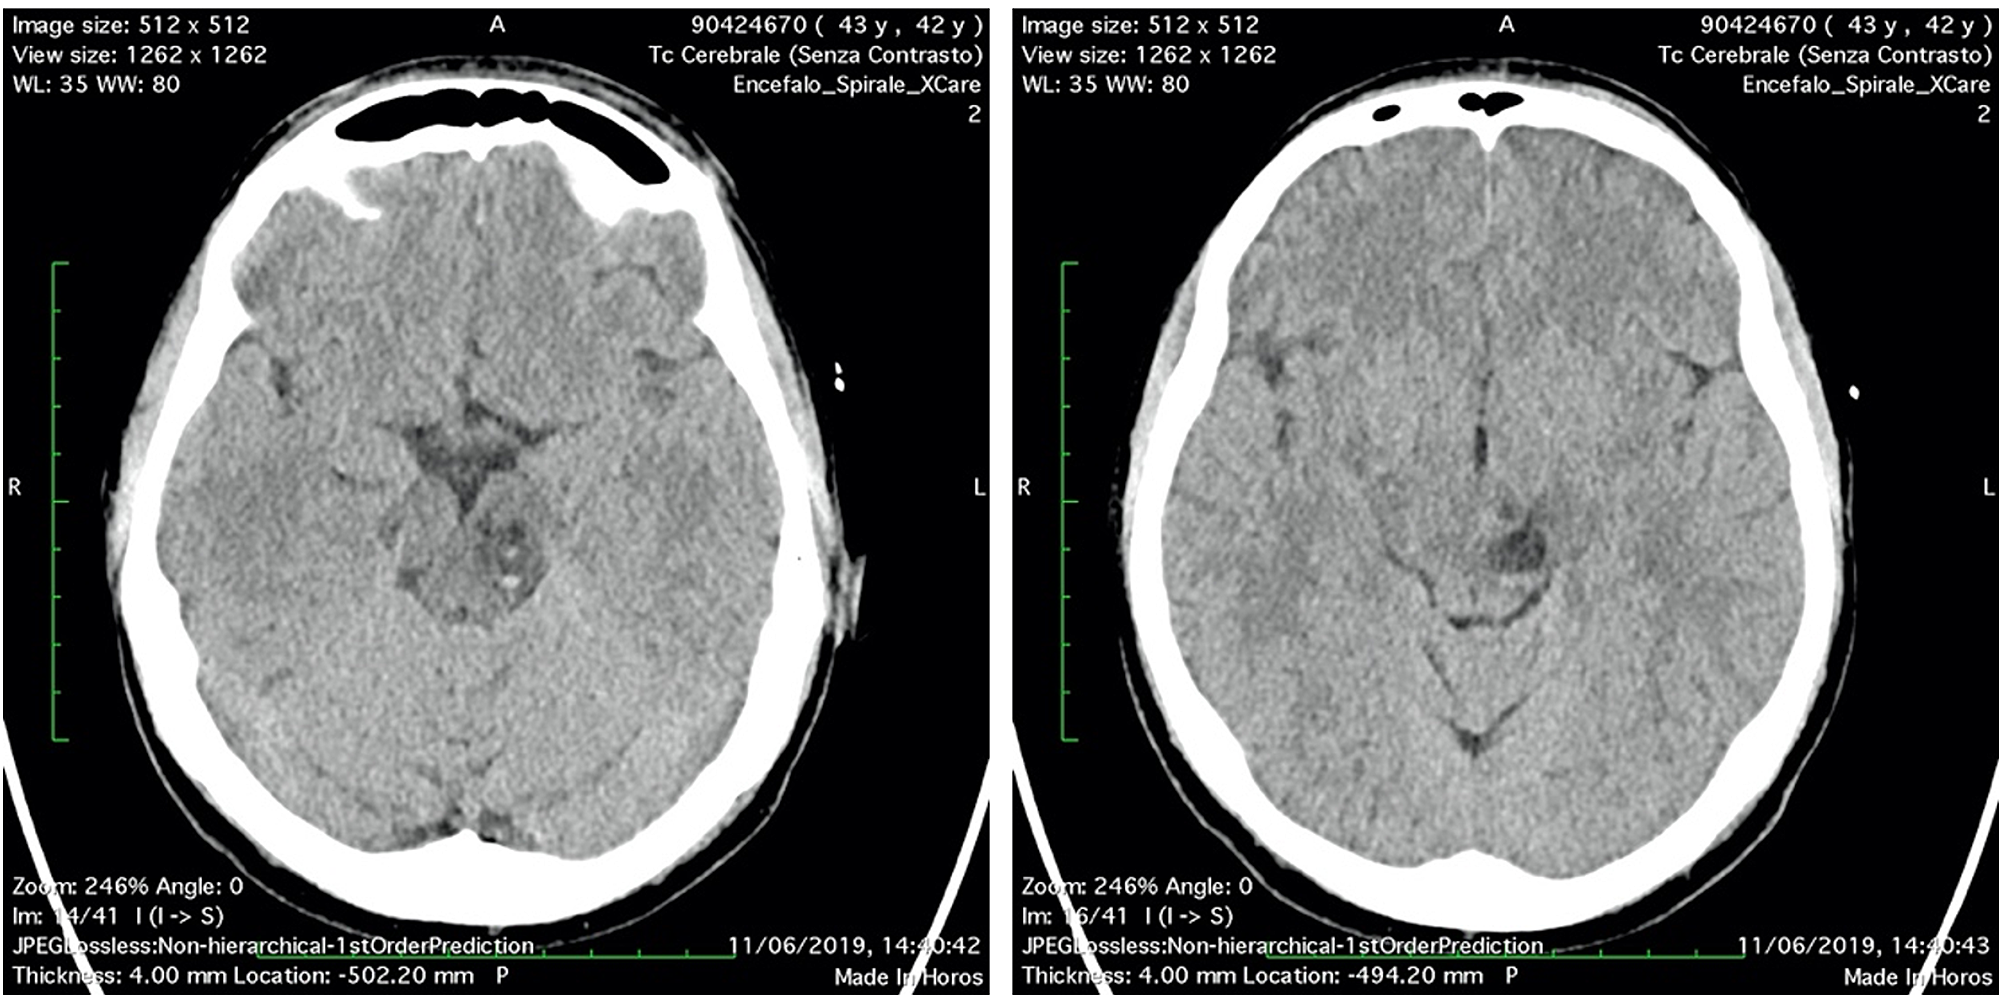

Two days after the surgery, diplopia and nausea were disappeared, vertigo persisted. The patient stayed six days more in hospital to follow the reconstruction of the scalp and to recover. Unfortunately, the patient had a reject of transplanted skin with necrosis and had to schedule a new surgery in a month later. Before discharge, a CT scan was performed in order to assess the midbrain lesion (Figure 4).